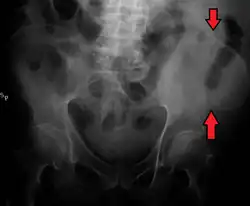

![]() Pelvic girdle. | |

The crest of the ilium (or iliac crest) is the superior border of the wing of ilium and the superolateral margin of the greater pelvis.

The top of the iliac crests also marks the level of the fourth lumbar vertebral body (L4), above or below which lumbar puncture may be performed. Furthermore, said level is often referred to as the "intercristal line".